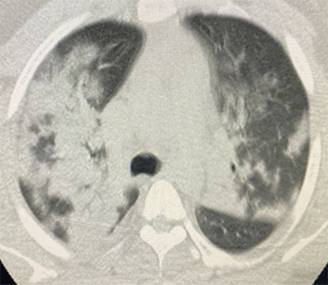

Presentamos una serie de casos de cuatro pacientes con SARS-CoV-2 con un compromiso importante de la oxigenación a pesar del uso de sistemas de alto flujo. En la Tabla 1 se describen grupos etarios, sexo, morbilidades, condiciones clínicas y escalas de severidad pronóstica de ingreso. Evolucionan tórpidamente frente al uso de cánula de alto flujo con índices de Rox por debajo de dos puntos en las primeras 12 horas.4 Se inicia ventilación mecánica no invasiva con progresión a falla respiratoria por aumento de la carga inspiratoria, por lo que requirieron protección de vía aérea. Se documenta un serio deterioro de la mecánica ventilatoria con sobredistención, aumento del trabajo respiratorio y caída de las distensibilidades; variables de monitoreo de la ventilación mecánica tomada en zona cero de flujo justo antes de cada inspiración. Adicionalmente evoluciona con importante deterioro de la ventilación minuto alveolar y de la oxigenación frente a la ventilación mecánica instaurada y a la posición prono, con poca tolerancia a la presión positiva direccionada por bucle presión volumen, meseta, fracción inspirada de oxígeno y curva presión tiempo.5-7 Con base en imágenes escanográficas que documentan infiltrados esmerilados, se describen cuatro campos pulmonares y zonas de condensación en las Figuras 1-4, además de compliance menor de 40 cm y requerimientos de PEEP entre 17 y 20 cm de agua, con el antecedente de volúmenes corregidos espiratorios durante la ventilación mecánica no invasiva entre 15 y 20 puntos se precisa SARS-CoV-2.8 Con base en la evolución descrita se decide instaurar protección pulmonar con 3 mL por kilogramo de peso más insuflación de gas traqueal con 5 L por min con el ánimo de ahorrar presión positiva de fin de espiración (PEEP por sus siglas en inglés positive end expiratory pressure), volumen tidal y velocidades de flujo. En la Tabla 2 se registra evolución gasimétrica antes y después de la estrategia. Se descartan coexistencias infecciosas de acuerdo al reporte de la microbiología. En los cuatro pacientes se documentaron defectos segmentarios de distribución vascular compatibles con enfermedad pulmonar tromboembólica. Evolucionan satisfactoriamente permitiendo desmontar estrategia de rescate con base en mecánica ventilatoria e índice de oxigenación,9 pudiendo implementar asa cerrada en asistencia proporcional con 40% de asistencia por flujo y volumen, PEEP de 10 cm y fracción inspirada de oxígeno de 50%. Se realizan monitoreos en asa cerrada que se muestran en la Tabla 3, documentándose trabajo respiratorio limítrofe, serio deterioro de las propiedades pulmonares mecánicas dinámicas y estáticas sin poder liberar de manera convencional, por lo que se programa para traqueostomía y traslado a cuidado crónico.

Figura 1: Condensaciones bronconeumónicas cuatro campos pulmonares. Colapso segmento lateral lóbulo medio. Imágenes subpleurales esmeriladas.